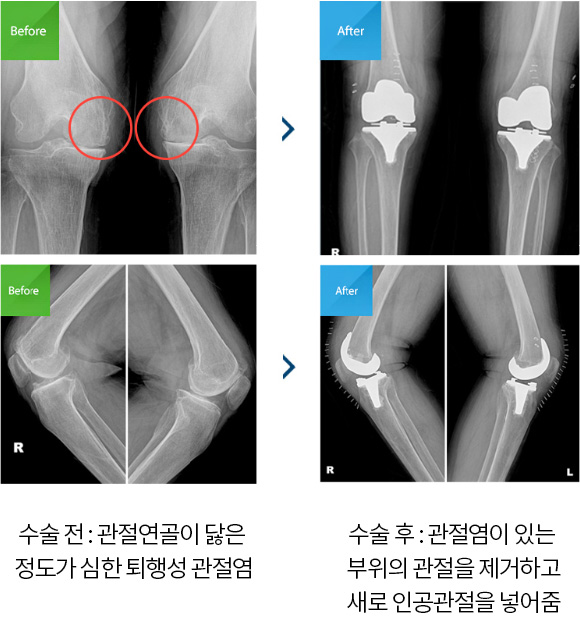

위 사진처럼 말기 관절염이란 관절염의 3~4기를 의미하는데 보통 연골의 역할(완충 역할)을 제대로 하지 못하고 닳아 없어진 경우를 말기 관절염이라고 부르게 됩니다.그럼 무릎 통증이 심해서 연골이 닳은 경우는 모두 이 수술을 하면 되나요??